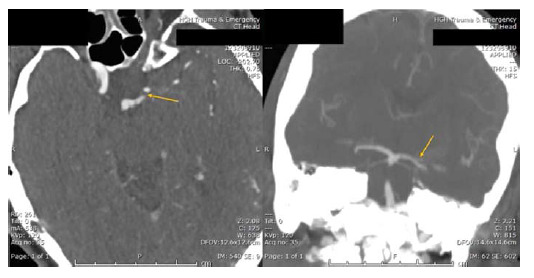

Clinical presentation: We report a case involving a 72-year-old female patient with AOP stroke characterized by a sudden loss of vision, followed by a decreased level of consciousness. Magnetic resonance imaging revealed bilateral thalamic infarcts sparing the midbrain. CTA (computed tomography angiography) revealed a filling defect at the origin of the Percheron artery arising from the left P1 segment. The patient was treated with intravenous thrombolysis. The stroke workup was unremarkable, with a normal thrombophilia workup, a transthoracic echo, and no arrhythmias detected on a prolonged Holter monitor. The patient was treated with aspirin, atorvastatin, and intensive physical and cognitive therapy. On follow-up, she regained her consciousness but exhibited residual impaired vertical eye movements and right-sided dysmetria.